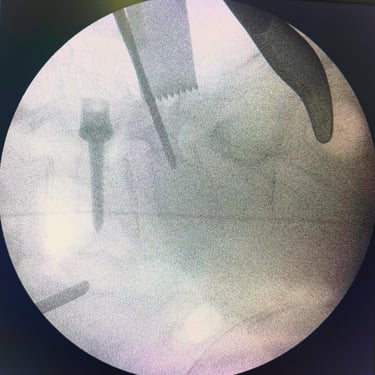

Listesis Lumbar: Artrodesis con Tornillos Transpediculares y Fusión Intersomática Transforaminal (TLIF).

La listesis lumbar es el deslizamiento anormal de una vértebra sobre otra, lo que puede generar dolor lumbar crónico, inestabilidad y compresión de las raíces nerviosas. Cuando el tratamiento conservador no es suficiente, la artrodesis con tornillos transpediculares (FTP) asociada a la fusión intersomática transforaminal (TLIF) es una técnica quirúrgica efectiva. Este procedimiento permite estabilizar la columna, restaurar la alineación vertebral y lograr una fusión sólida, al mismo tiempo que descomprime las estructuras nerviosas. La combinación de estas técnicas mejora el control del dolor, la función neurológica y la calidad de vida del paciente.